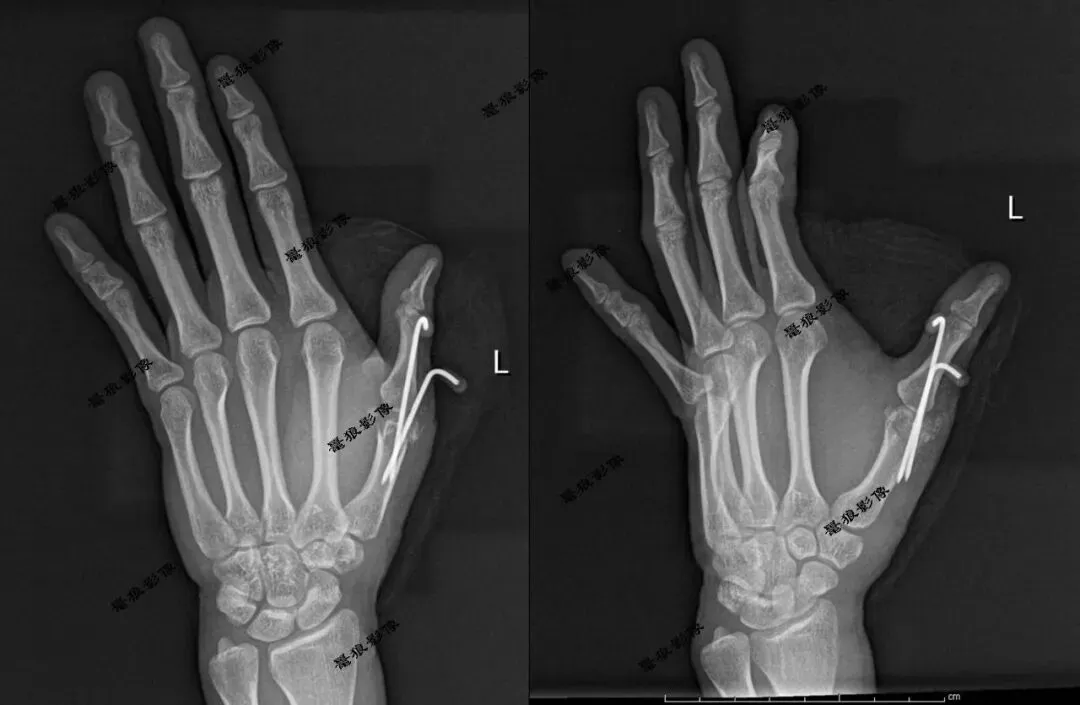

一、左手第1指多指畸形。

案例一:术后